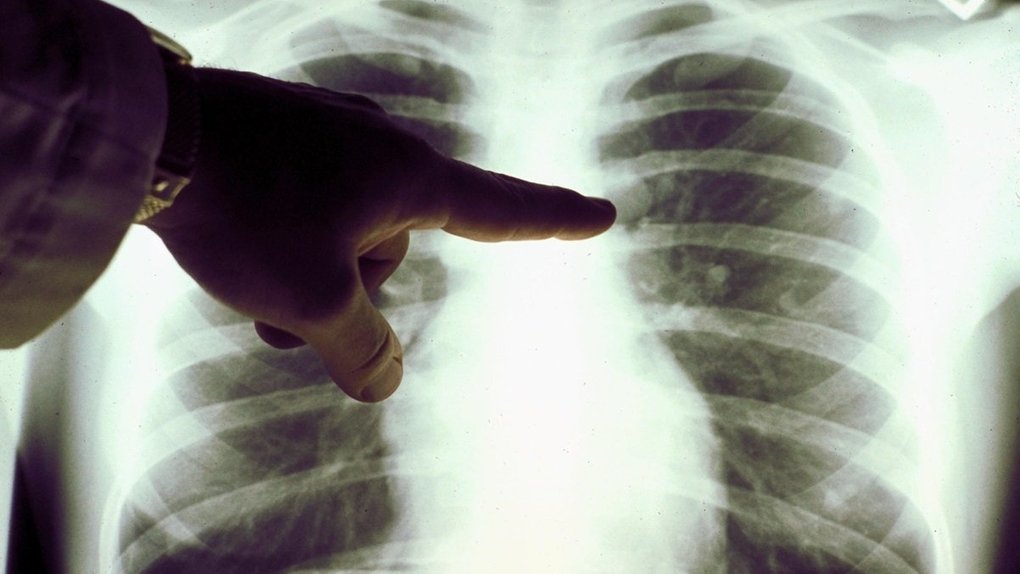

Пневмонія – це запалення легеневої тканини, що унеможливлює нормальний газообмін через накопичення рідини та гною в альвеолах. Найуразливіші категорії – діти, люди літнього віку та пацієнти з хронічними захворюваннями.

Основні симптоми пневмонії включають кашель із харкотинням, високу температуру, біль у грудях, задишку, слабкість, пітливість і зниження тиску. У тяжких випадках з’являються неприємний запах харкотиння, часте поверхневе дихання, нудота та блювота.